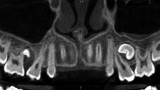

Resorpcja zęba to proces powstania ubytku twardych struktur zęba wywołanego przez osteoklasty bez kontaktu ze środowiskiem jamy ustnej, między innymi na skutek ucisku wywieranego przez ząb zatrzymany. Dla lekarza ortodonty jest istotne ustalenie, czy zęby zatrzymane lub twory nadliczbowe powodują resorpcję zębów stojących w łuku w celu wczesnej eliminacji przyczyny resorpcji. Celem pracy jest przedstawienie opisu przypadku zastosowania tomografii stożkowej w diagnostyce nieprawidłowo położonych zawiązków zębów przedtrzonowych drugich górnych. Stwierdzono, że tomografia stożkowa jest skuteczną metodą oceny wczesnej resorpcji zewnętrznej korzeni zębów.

Tooth resorption is the process of appearing of a defect of hard tissues of teeth caused by osteoclasts not having contact with oral cavity environment, eg. due to mechanical pressure exerted by an impacted tooth. It is essential for an orthodontist whether impacted teeth or supplementary teeth cause resorption of erupted teeth in order to early eliminate the causative factor of the resorption. The aim of the paper is to describe a case report of cone-beam computed tomography (CBCT) in diagnostics of incorrectly located germs of upper second premolars. It was found that CBCT was an efficient method of imaging of early external root resorption.